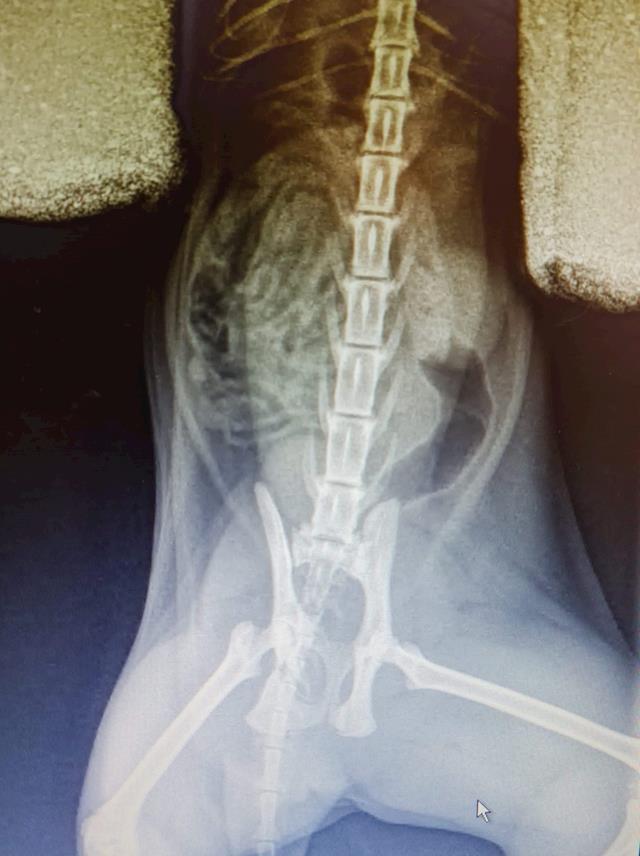

Main image

Went to visit Bernie today at Karorir Veterinary Clinic. X-rays show her pelvis is worse than thought in terms of narrowing, plus 2 fractures they could see. The left pelvic bone is fine, but the right one is angled very narrow. It means a hit and run is likely what caused the injuries. She has been put on pain medication and anti inflamatories, but they were unable to get her on a drip or properly fix a catheter.

A request with the Massey University Animal Surgery department was made today, and they will ring me with an update on the procedure from here sometime tomorrow. They will do further x-rays to make sure there aren't any joint fractures.